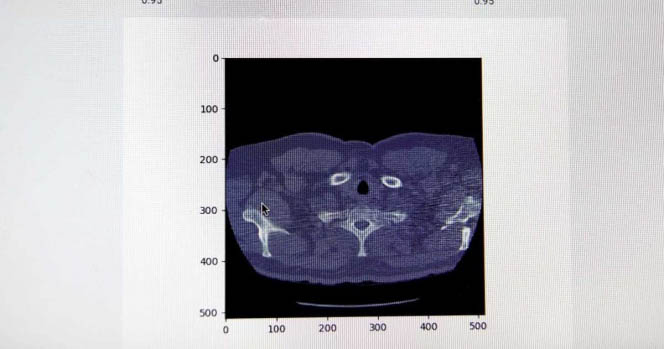

Crea IPN sistema para detectar cáncer de pulmón

Estudiantes de la ESCOM entrenan algoritmos que reconocen anomalías en pulmones; la herramienta analiza imágenes de tomografías y las clasifica para apoyar a médicos en sus diagnósticos